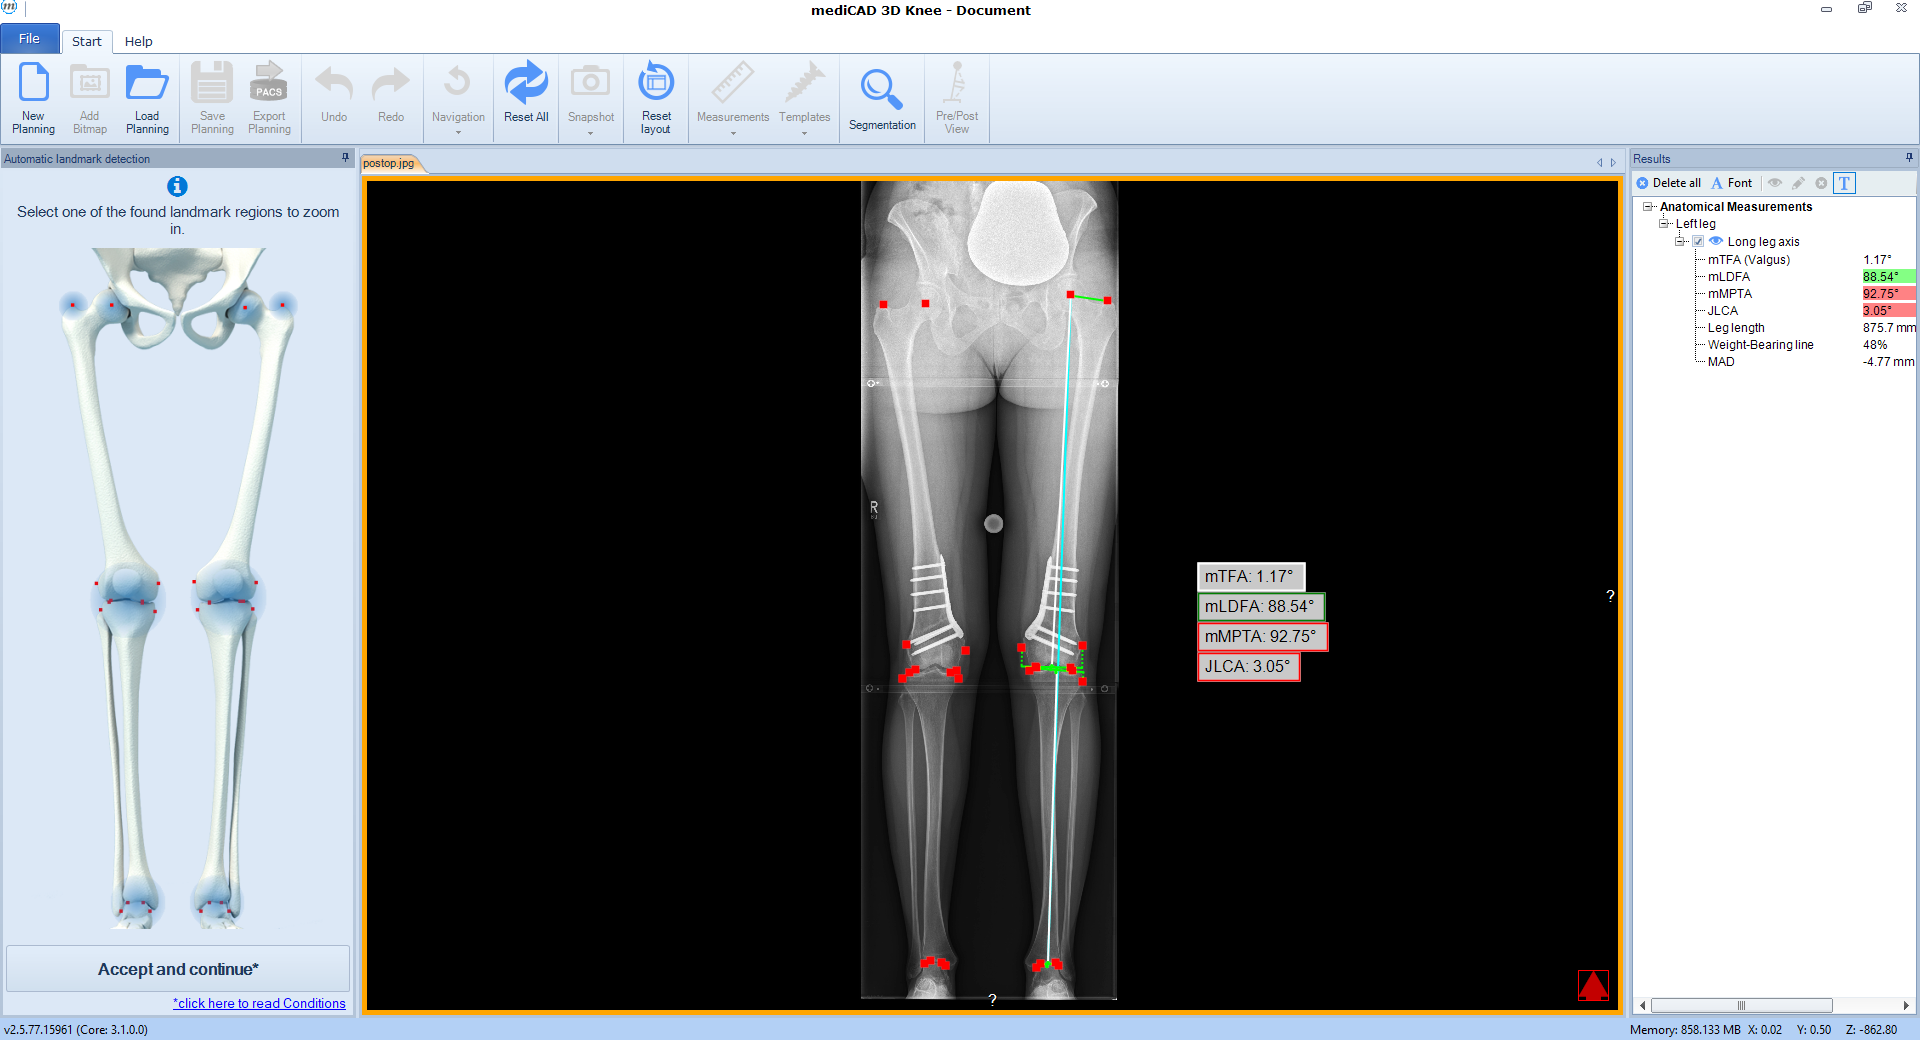

The software automatically detects all necessary landmarks (Fig 1). Based on their position (which can be adjusted manually) the software calculates all essential values (axis, joint lines, and angles) and delivers a detailed report. A traffic light system illustrates normal, intermediate, or pathological values.

Following the deformity analysis, the software automatically recommends a surgical procedure, eg, medial opening wedge high tibia osteotomy, depending on the type of deformity (Fig 2). The user can follow the proposed procedure or choose individual options.